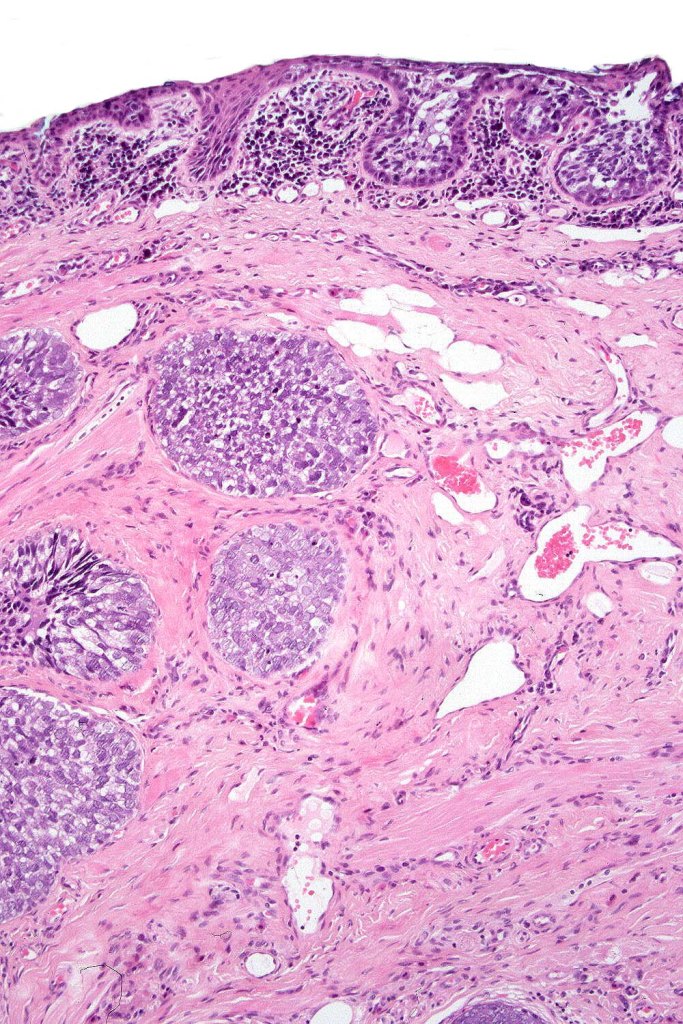

•Well differentiated lobular growth pattern though to a poorly differentiated tumor often showing a diffuse, infiltrating border which may extend into the subcutaneous fat

•Comedo type necrosis commonly present

•Tumors are composed of an admixture of darkly staining basaloid cells with hyperchromatic or vesicular nuclei and more obvious sebaceous cells with eosinophilic, bubbly, multivacuolated cytoplasm frequently indenting the nucleus (scalloped)

•Often mitoses are numerous and abnormal forms evident

•Variable Lymphovascular invasion & perineural infiltration